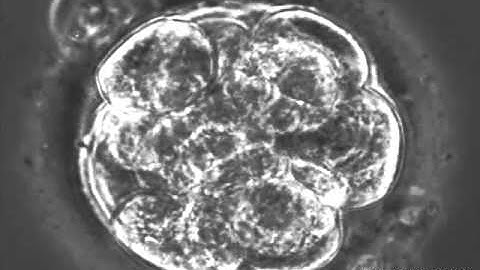

Time lapse imaging of fertilized mouse egg utilizing AI